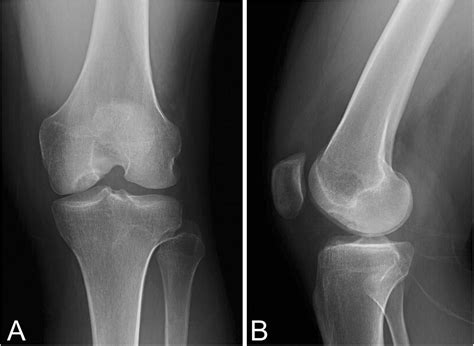

Nov 27, 2025 · An osteochondral lesion (OCL) describes damage that affects two distinct tissues within a joint: the articular cartilage and the underlying subchondral bone. This condition is a common. Jan 23, 2022 · Osteochondral lesions are injuries or defects that affect the cartilage and the underlying bone in a joint. These lesions can occur due to trauma, repetitive stress, or degenerative conditions. Aug 2, 2025 · An osteochondral lesion is an injury affecting a joint, specifically involving damage to both the cartilage and the underlying bone. These lesions are a localized defect within the joint’s surface.. About osteochondral defects An osteochondral defect is a localised area of surface cartilage damage. This also involves the underlying bone (osteo) beneath the surface cartilage and the overlying shock. Mar 11, 2025 · Osteochondral defects in the knee involve a complex interplay of damaged articular cartilage and underlying bone. While they can develop from acute injury, chronic overuse, or.

Osteochondritis dissecans is an idiopathic disease which affects the subchondral bone and its overlying articular cartilage due to loss of blood flow. [1] This may result in separation and. Dealing with osteochondral injuries? OS Clinic’s expert orthopaedic surgeons provide advanced treatments for cartilage damage and joint repair. Book a consultation today. Chondral osteochondral defect, a knee injury, causing pain, swelling, and catching of the joint. The joint feels unstable and won’t straighten fully. Oct 18, 2023 · What Is an Osteochondral Fracture? Injuries or damage on the articular surface of a joint are known as osteochondral fractures or transchondral fractures. An osteochondral fracture is an.